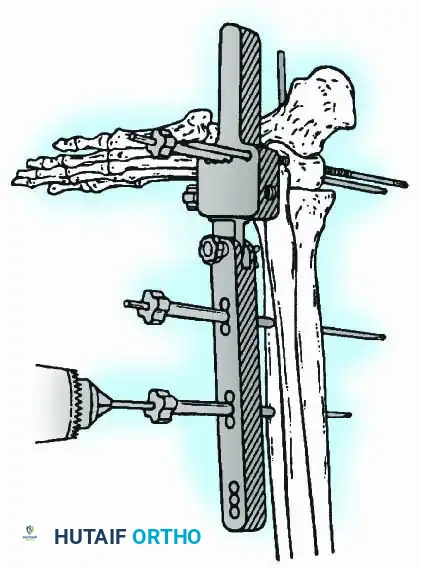

External Fixation

Historically pioneered by Charnley, external compression arthrodesis utilizes pins placed through the distal tibia and the body of the talus. Because Charnley's original uniplanar device lacked rotatory stability, Calandruccio designed a triangular frame to control motion in all three planes while applying massive compression.

Modern iterations, such as the Calandruccio II compression device, offer greater latitude in pin placement to avoid compromised skin. Ring or circular external fixators (Ilizarov, Taylor Spatial Frame) are the gold standard for salvage situations, including active infection, massive bone loss, or failed TAA, as they allow for simultaneous compression, deformity correction, and early weight-bearing.